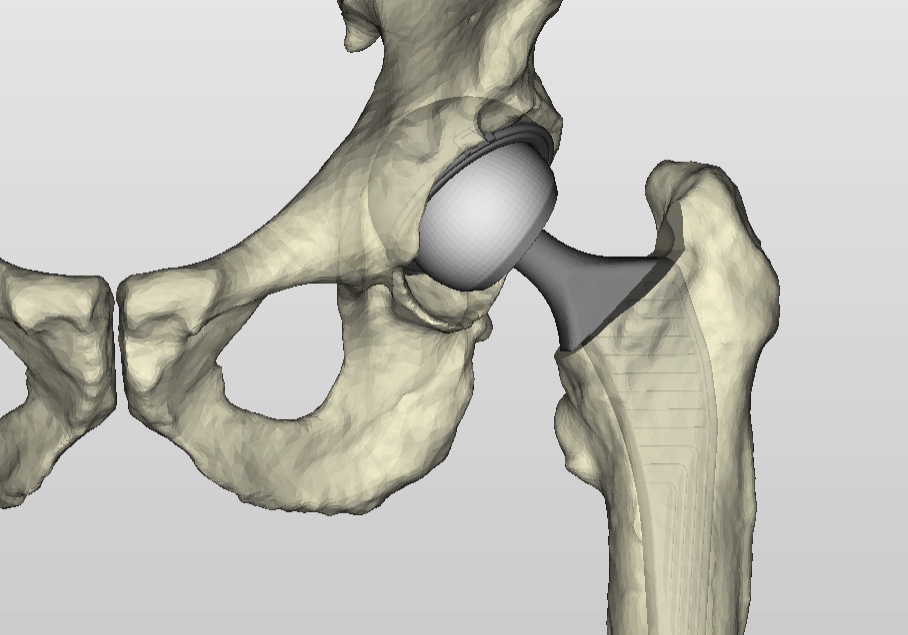

Απόλυτη ακρίβεια με προεγχειρητικό σχεδιασμό

Η απόλυτη ακρίβεια στην επιλογή του μεγέθους των προθέσεων και στην ιδανική τοποθέτηση της, επιτυγχάνεται με τον προεγχειρητικό σχεδιασμό της επέμβασης και την εξατομίκευση της ολικής αρθροπλαστικής. Γίνεται ανάλυση της ανατομίας με 3D αξονική τομογραφία και επιλογή της ιδανικότερης πρόθεσης.